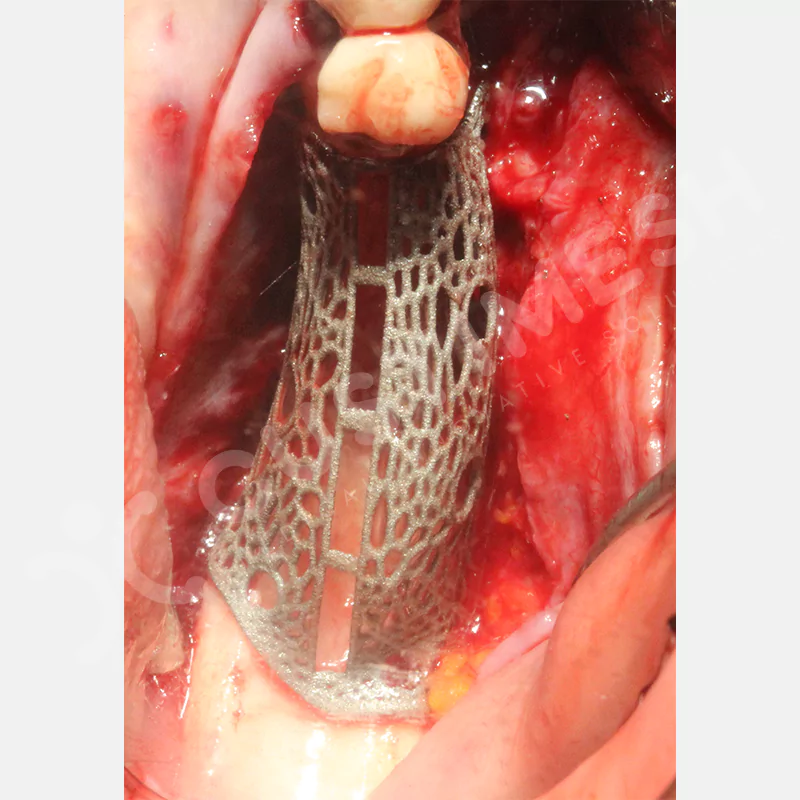

Dental implant uygulanamayan hastalarda kemik rejenerasyonunu sağlamak üzere geliştirilen kişiye özel titanyum mesh, kemik augmentasyon işlemlerinde greft materyalinin korunması ve yeni kemik oluşumunun desteklenmesi amacıyla kullanılan, hastanın kendi anatomisine tam uyumlu titanyum bir bariyer sistemidir.

Medikal sınıf titanyumdan, hastanın bilgisayarlı tomografi verileri kullanılarak CAD yazılımlarıyla tasarlanan ve 3D baskı teknolojisiyle üretilen bu yenilikçi çözüm, özellikle kompleks kemik defektlerinde standart meshlerin sağlayamadığı üstün mekanik stabilite ve mükemmel adaptasyon özellikleri sunar. Anatomik yapıya tam uyum sağlayarak greft materyalinin yerinde kalmasını garanti ederken, optimal vaskülerizasyonu destekleyerek kemik rejenerasyon sürecini hızlandırır.